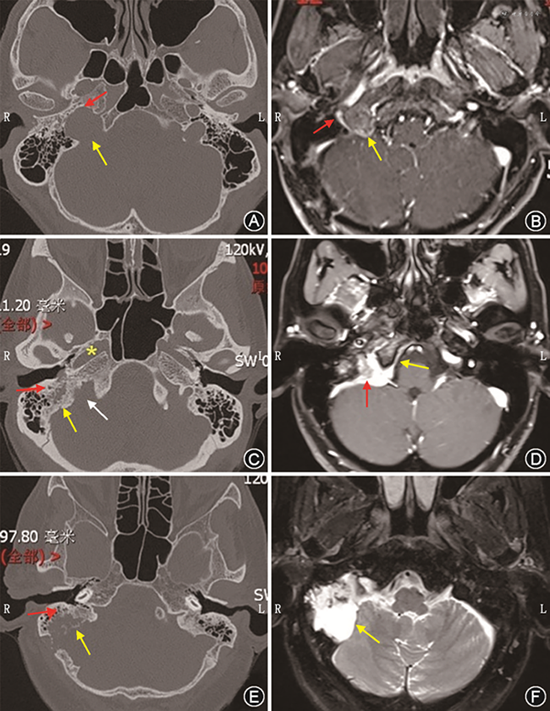

神经鞘瘤是膨胀性生长的肿瘤,血供较副神经节瘤差,瘤内可有大小不等的囊变区,颞骨CT平扫示颈静脉孔扩大,边缘骨质光滑完整(图3A);颞骨MRI检查在T1WI上肿瘤呈等或稍低信号,边界清楚,病灶内囊变区呈更低信号,T2WI呈高信号或信号不均匀,增强MRI可见肿瘤不同程度增强。增强后瘤体中央囊变明显者表现为环状或蛋壳样强化,囊变不明显者表现为均匀或不均匀强化。由于肿瘤起源于颈静脉球内侧壁深面,增强后可见肿瘤将颈静脉球向后上方推压,同时将上颈部的颈内动脉向前内侧推压(图3B)。

2.脑膜瘤:颈静脉孔区脑膜瘤主要起源于颈静脉孔区蛛网膜绒毛细胞,发生率占颈静脉孔区肿瘤的5.3%,仅次于副神经节瘤、神经鞘瘤,该部位脑膜瘤生长缓慢,但与副神经节瘤相比易复发。颞骨CT可表现为颈静脉孔骨质被肿瘤侵蚀破坏,同时可有骨质增生(图3C);MRI表现为T1WI在血管丰富时高信号,纤维组织丰富时等或低信号,增强后见肿瘤明显均匀强化,同时可见脑膜尾征,多数肿瘤呈匍匐状生长,常紧贴颅骨、硬脑膜,基底较宽,颅外部分可环绕颈动脉鞘生长(图3D);DSA检查有助于了解周围血供情况,对于排除副神经节瘤很有帮助,但常无法区别脑膜瘤和神经鞘瘤,术前明确颈静脉孔是否闭塞对于手术操作有重要的意义。

颈静脉孔区软骨肉瘤在高分辨CT上表现为颈静脉孔边缘骨质不规则破坏,病灶内可出现钙化斑(图3E),为颈静脉孔软骨肉瘤特征性表现,在诊断上有重要指导意义;在MRI T1WI序列为等信号,T2WI序列为高信号,增强后强化不均匀(图3F)[20]。我们的一项回顾性研究中,所有病例均出现病灶钙化斑,这有助于与面神经瘤进行鉴别诊断,面神经瘤也可侵及颈静脉孔及腮腺深叶,但病灶中无钙化斑[19]。